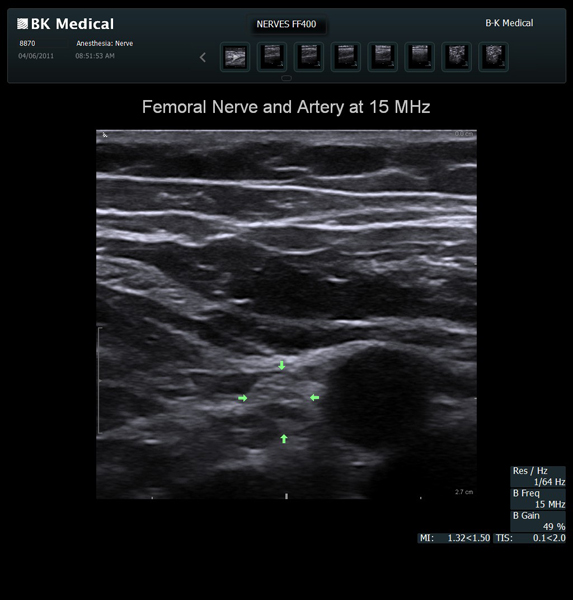

Enhanced Needle Visibility with Innovative X-Shine

X-Shine needle visualization option enhances the needle’s appearance in real time during in-plane procedures.

Transducers Designed for Guidance

BK Medical offers high-frequency linear transducers, imaging from 18-2 MHz for upper and lower extremities, and curved array abdominal transducer 8820e for special deep nerves or paravertebral/spinal applications. Our transducers provide superb detail that makes it easy to see your needle during procedures.